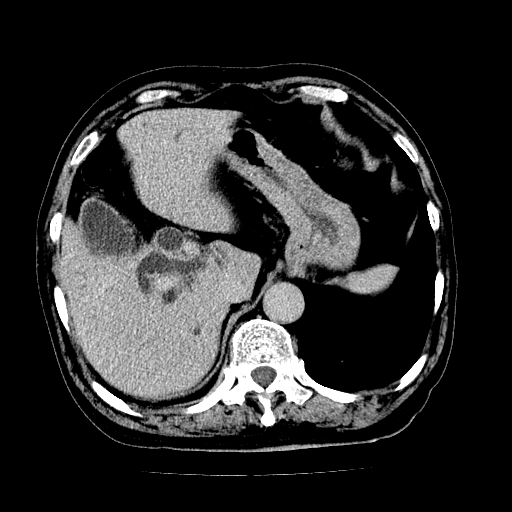

男,71岁,皮肤黄染四天。

肝内外胆管及胆总管上段扩张,考虑为梗阻所致,建议mrcp检查。

考虑胆总管癌并肝内外胆管扩张。

胰腺上端胆总管内见软组织影,强化不明显,结合临床,还是考虑低位梗阻性黄疸,胆总管癌可能性大